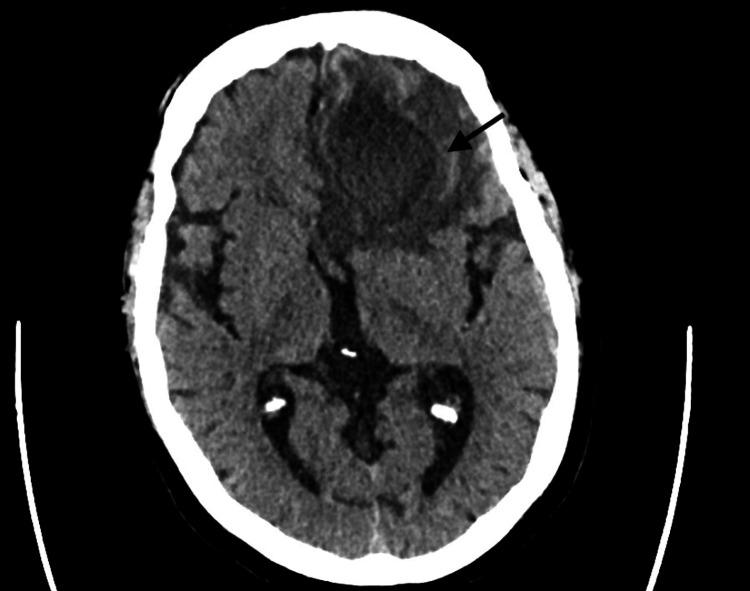

species are aerobic, gram-positive, filamentous bacteria. Infection occurs either through inhalation leading to pulmonary symptoms or inoculation presenting with skin findings. Hematogenous dissemination, although uncommon, is possible and can lead to central nervous system involvement.  brain abscess is a rare manifestation that comprises 2% of all brain abscess etiologies, mostly occurring in immunocompromised patients. Establishing a diagnosis is often difficult, especially due to its rare occurrence and the fact that it can mimic other etiologies on brain imaging including necrotic tumors. High mortality rates have been reported due to delays in establishing a diagnosis and a lack of precise treatment guidelines.

该菌为需氧、革兰氏阳性丝状菌。感染可通过吸入导致肺部症状,或通过接种出现皮肤表现。血行播散虽不常见,但有可能发生,并可导致中枢神经系统受累。脑脓肿是一种罕见表现,占所有脑脓肿病因的2%,主要发生在免疫功能低下的患者中。诊断往往很困难,尤其是因其罕见,且在脑部影像学上可类似其他病因,包括坏死性肿瘤。据报道,由于诊断延误和缺乏精确的治疗指南,死亡率很高。